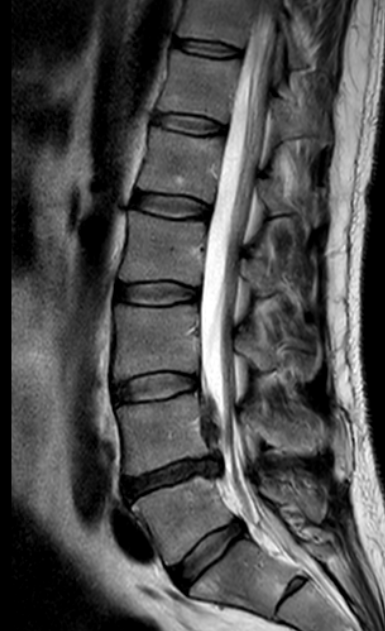

In 1999, aged 19, I suffered a major spinal injury. A discectomy saved me from losing function in my legs, and for nearly two decades I did well — despite the odd flare-up, I worked hard, built Delphian, and followed all the advice: stay strong, stay fit, maintain a good core. Then during the 2020 lockdown, I re-injured myself. An MRI was done — but the results were never communicated to me. I wasn’t told that the same disc operated on in 1999 had seriously degenerated and herniated. I just carried on: deadlines, family life, recording sessions. But the disc height was decreasing, pain was increasing, and over the next five years I had to stop rowing, running, swimming and eventually leave the gym. In early February, I picked Samuel up from his travel cot — and couldn’t walk for a week. Things unravelled properly in April. A major herniation during a recording trip left me barely able to walk. Disc material had migrated upward into my spinal canal, causing severe nerve compression. The pain was constant. My left had begun to waste away. For weeks, I needed a crutch, and every step was painful. In the past few weeks, the pain has finally begun to subside as the nerve agitation settled to a new norm. But the nerve compression has taken its toll. I’ve now lost almost all sensation below the thigh in my left leg — walking is exhausting, and I often trip over door thresholds I can’t feel. The reduced pain is welcome, but the risk of permanent damage is now very real. Thanks to the extraordinary generosity of friends, family and colleagues, I’ve just undergone surgery in Düsseldorf. I’m writing this on day two post-op. The plan had been to replace the damaged disc at L4/5 — but after meeting me in person, my surgeon, Dr Schmitz, determined that the next level down (L5/S1) was already severely bulging against my spinal cord and likely to fail within months. The decision was made at the 11th hour to replace both discs. That added £8,000 to the bill — but post-surgery, he told me plainly: “That disc was looking round the corner.” The operation took three and a half hours. I’m now beginning the long recovery — seven days in Germany (the clinic have kindly said ai can stay longer at no extra cost if pain levels haven’t settled), followed by months of healing and rehab back home. I’ll need three months of rest before physical therapy. At six months, the prostheses should be fully integrated and I should be beginning my new normal; by month twelve, I’ll be able to resume full physical activity with no limitations. For he first time in decades I ought to be able to put in socks and shoes without pain.